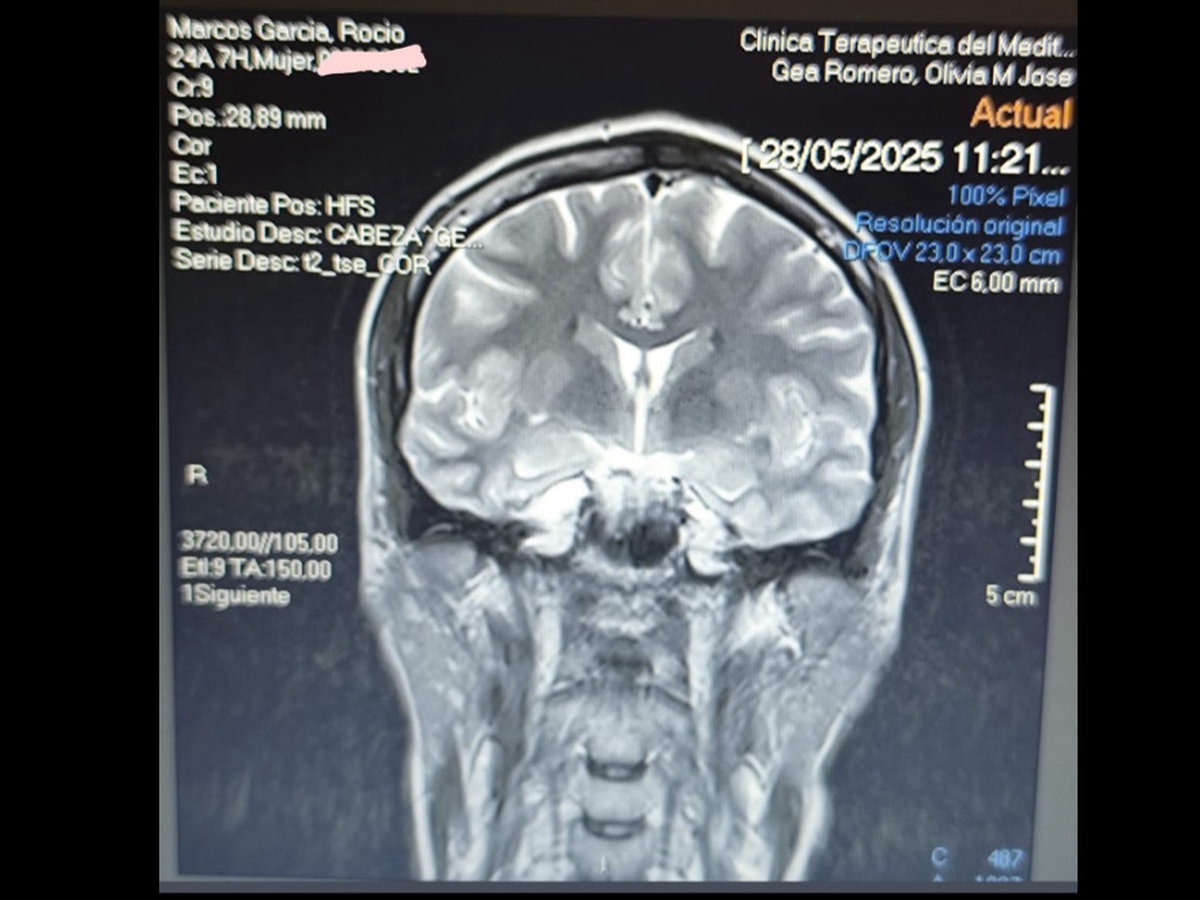

Hola, me llamo Rocio y hace poco me dijeron que tenía un quiste aracnoideo cerebral, hago esta recaudación de fondos ya que al trabajar en el ejército no puedo ir por lo público, he conseguido que me operen a principios de julio pero la operación tiene un precio bastante costoso, por lo cual toda ayuda que me deis os la agradecería muchísimo, muchas gracias a todos de antemano.